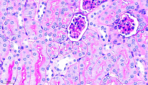

PAS_Mouse-Kidney__viewcapture-3